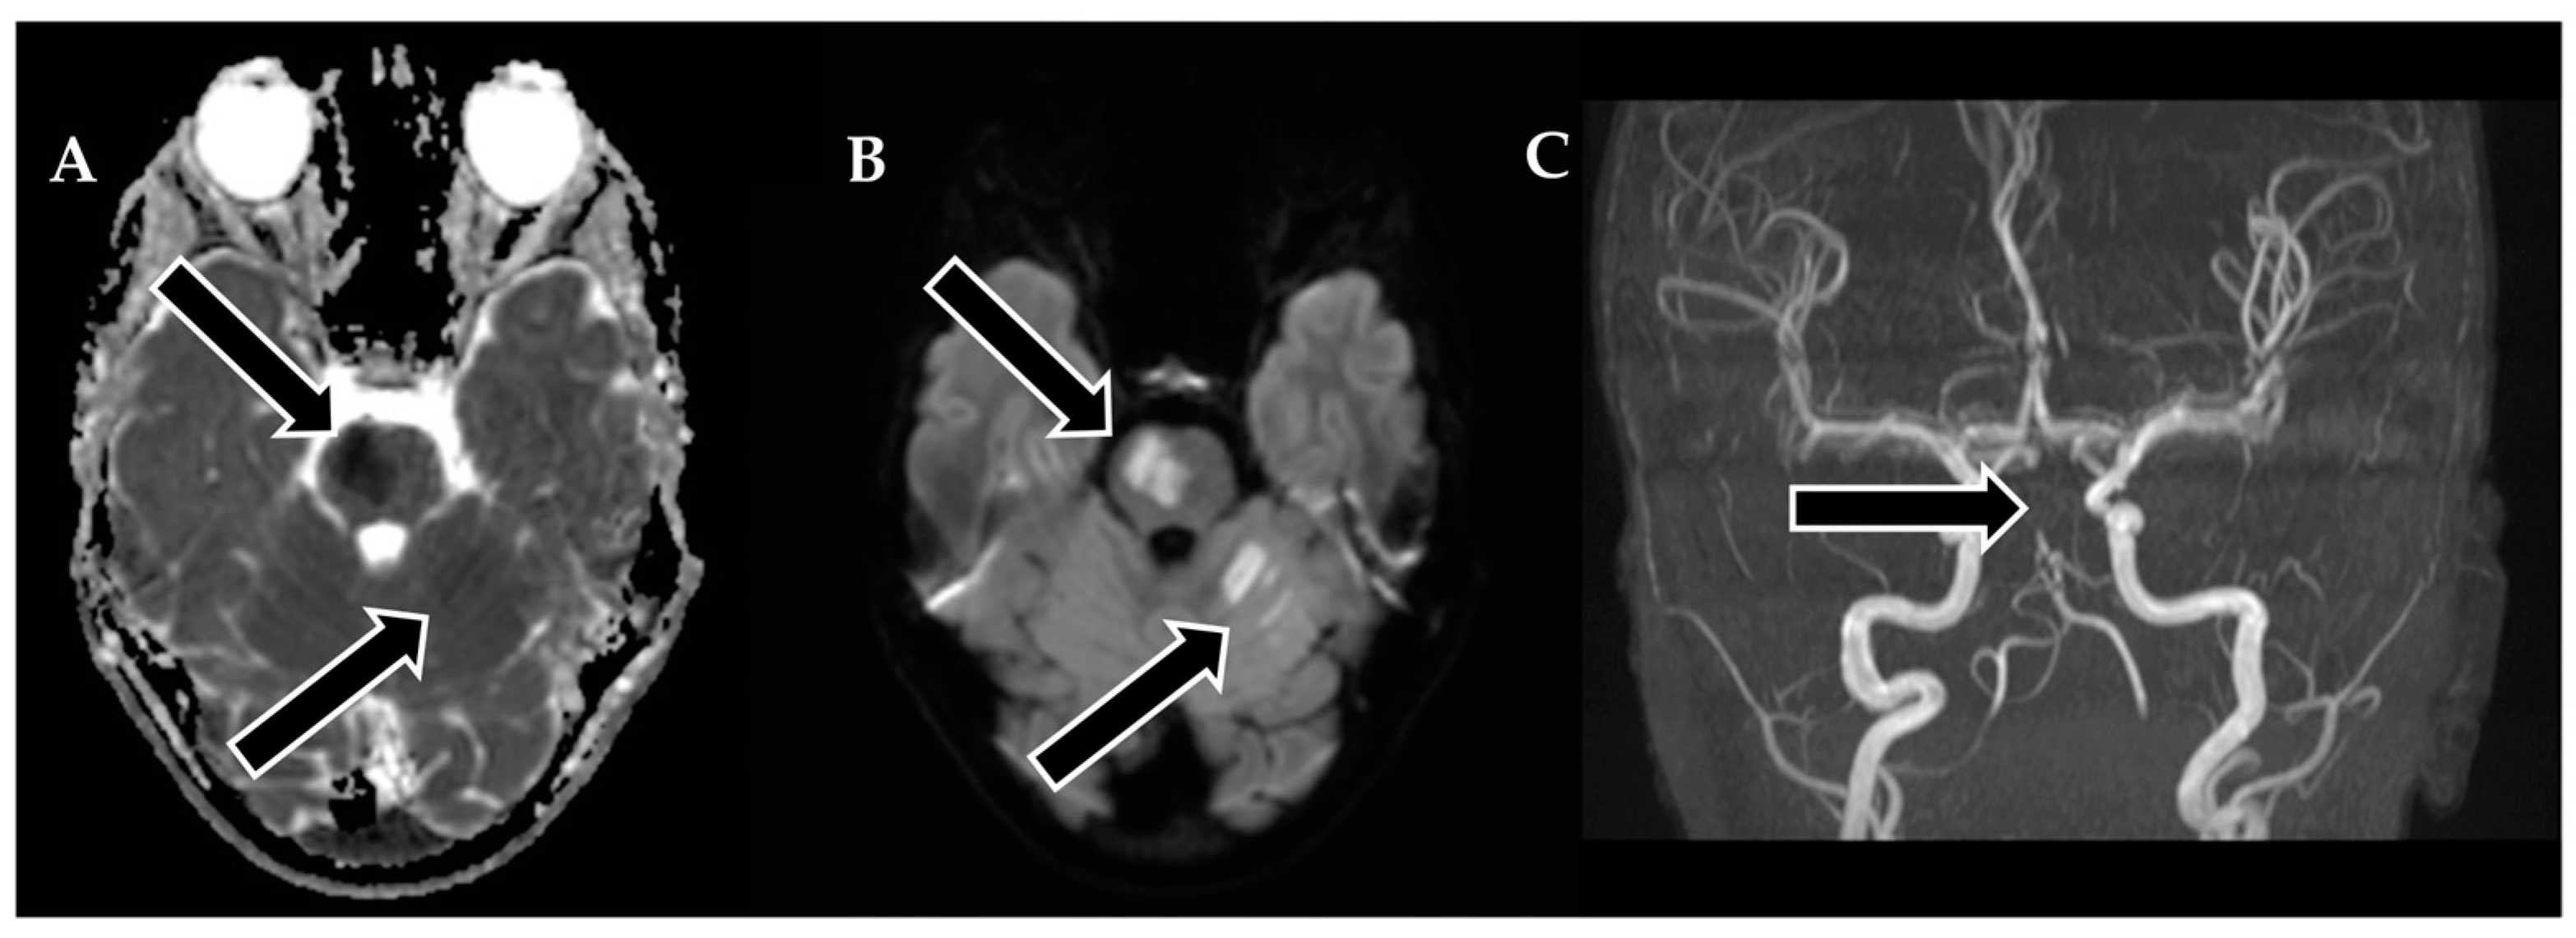

During the six-month follow-up, the patient exhibited a complete neurological recovery, as evidenced by an NIHSS score of 0 and an mRS score of 0. An MRI scan conducted at this time (Figure 6) revealed scarring with hypointense areas on the right pons in the FLAIR sequence. Importantly, magnetic resonance angiography (MRA) confirmed unobstructed flow in the basilar artery. This positive outcome marked a significant milestone in the patient’s journey toward recovery and underlined the remarkable resilience of the young patient in overcoming the challenges posed by this enigmatic stroke.

Figure 6. Follow-up MRI of the brain approximately 6 months after thrombectomy. (A) Markedly hypointense areas on the right side of the pons in the FLAIR sequence, indicating scarring. Corresponding hyperintense changes are observed on: (C) T2-weighted images, with a distinct hyperintense area on the right side of the pons (arrow). (B) Changes in the upper part of the left cerebellar hemisphere are visible in the FLAIR sequence. (D) An MRA examination shows unobstructed flow in the basilar artery and both cerebral posterior arteries.